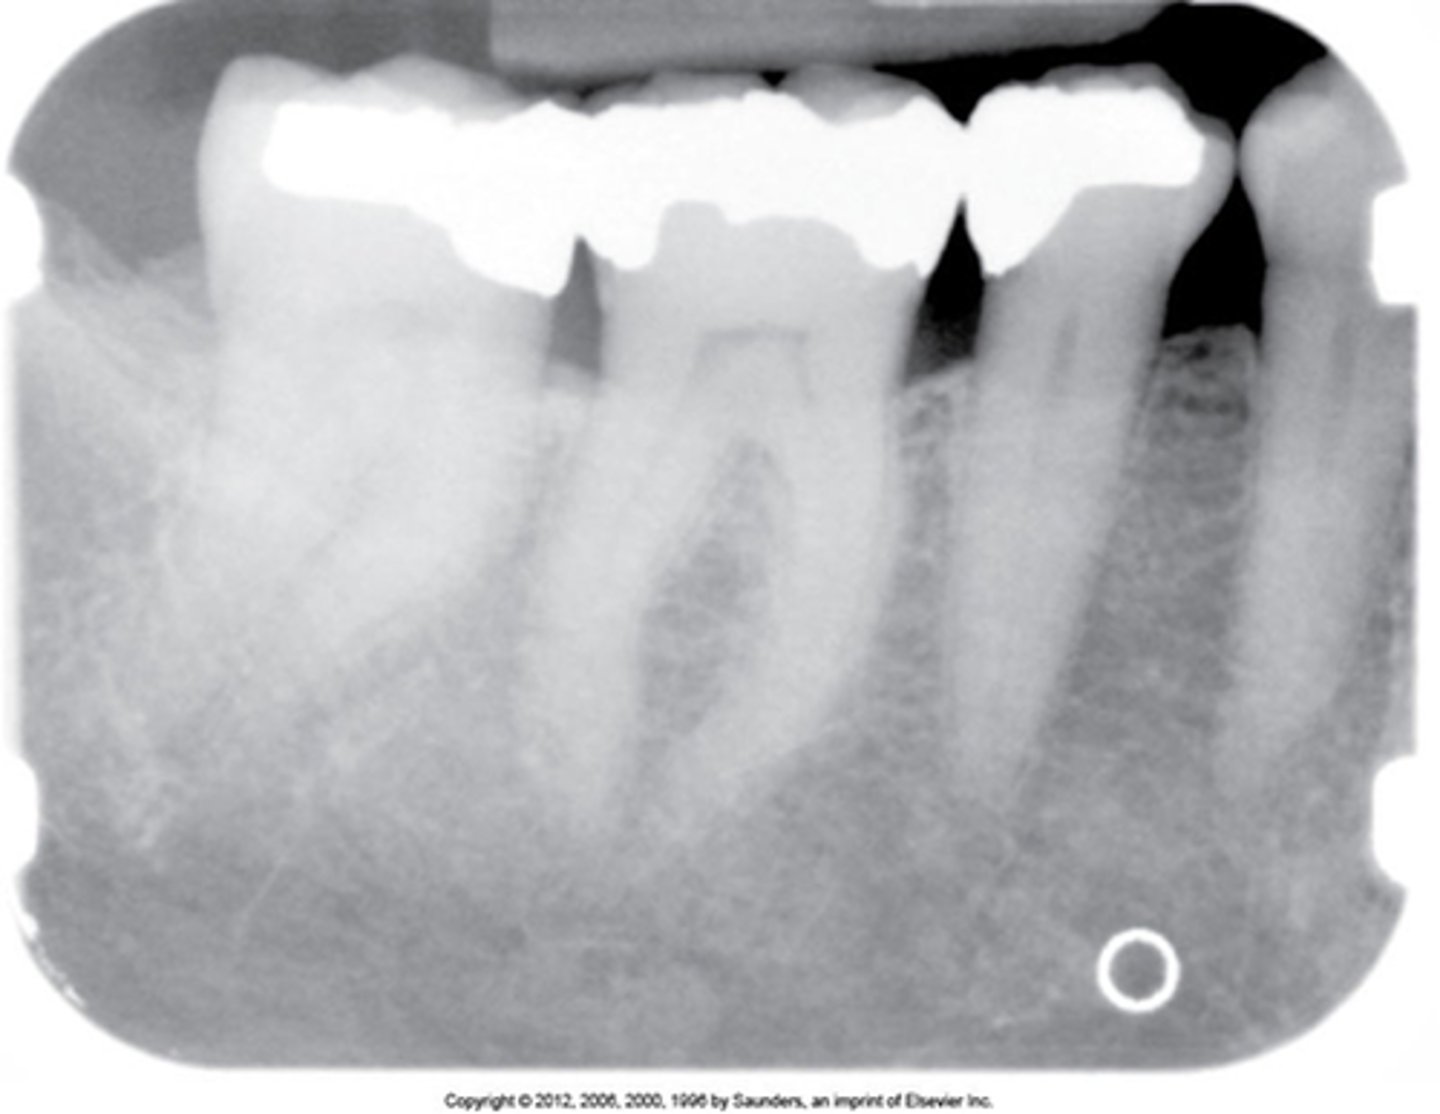

MOD amalgam

overhang

PINS

decay

calculus

crown prep